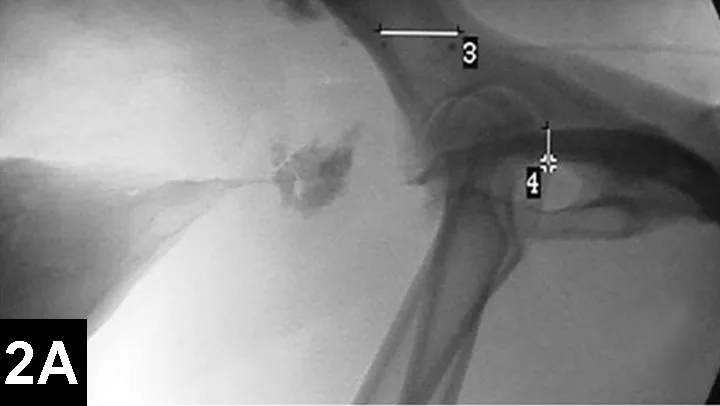

Figure 2A: Serial lateral positive contrast urethrocystograms in a dog with a malignant urethral obstruction secondary to a prostatic tumor.

Maximal urethral diameters measured using a colonic marker catheter to adjust for radiographic magnification.

IR techniques that involve placement of an intraluminal stent to alleviate signs associated with malignant obstructions have been described in veterinary patients (Figure 2).5 The author has performed multiple palliative stenting procedures in the urinary tract and upper and lower GI tracts and has relieved luminal obstructions caused by neoplasia or intractable benign strictures in many different sizes of animals, including ferrets.5-11 The IR techniques were fast, safe, and effective. Complications were minor and uncommon.